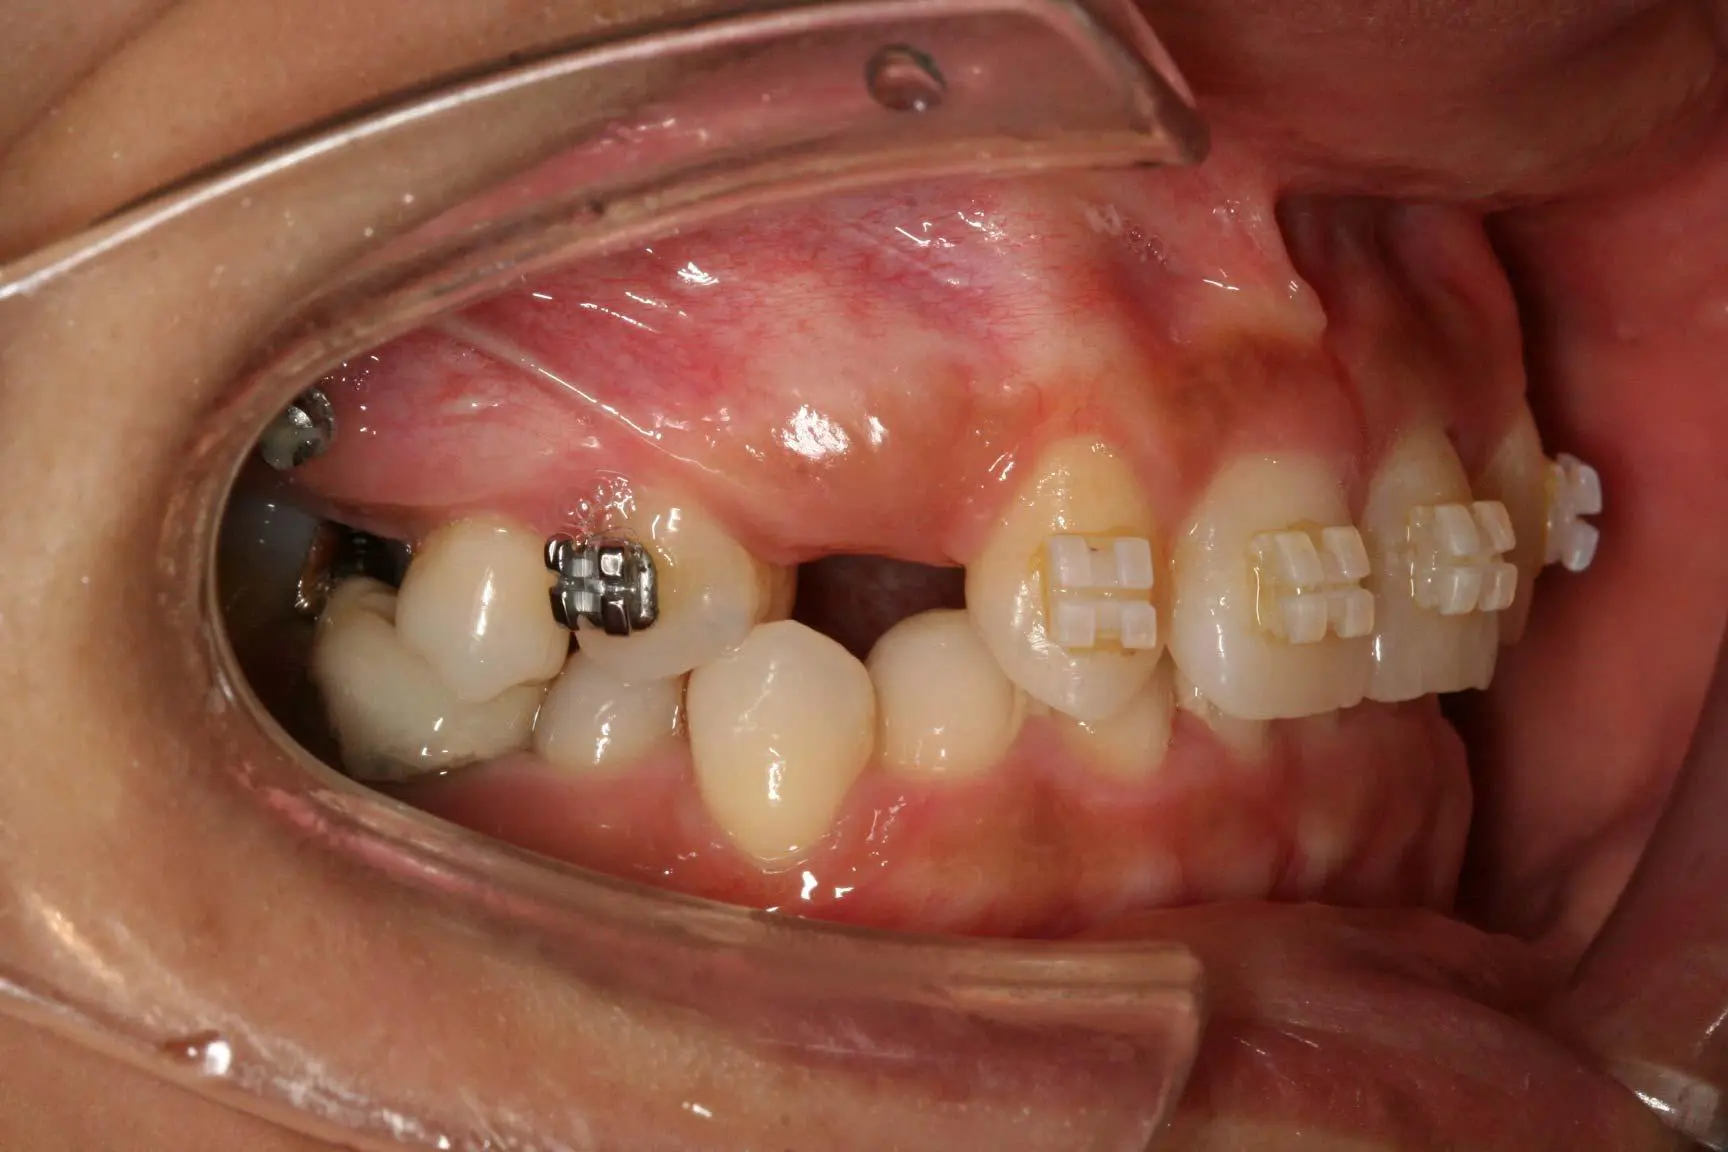

先天性欠損によるインプラント治療

年齢 20歳 性別 男性

治療期間 2ヵ月 費用 800,000円

先天性欠損によるインプラント治療 先天性欠損によるインプラント治療